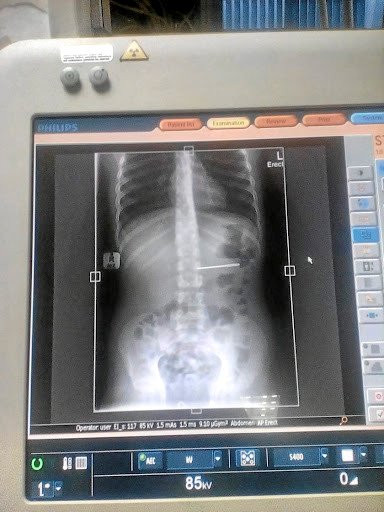

Hình ảnh chụp X-quang cho thấy chiếc kim nằm trong dạ dày nạn nhân. (Ảnh: Timeslive)